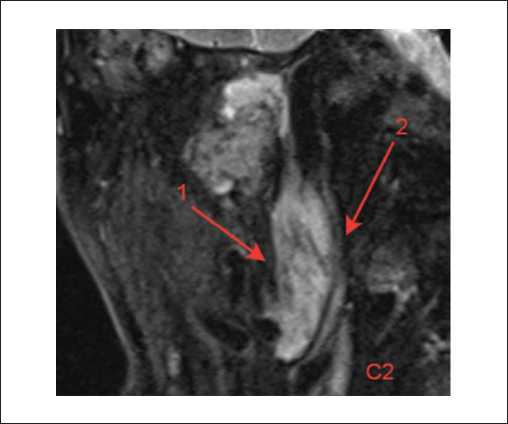

Пациенты третьей группы с диагностированной распространенной параганглиомой предъявляли жалобы на отсутствие слуха с пораженной стороны, периодическое онемение лица, периодические эпизоды кровотечения из слухового прохода. У 6 пациентов, которые до поступления в нашу клинику неоднократно подвергались хирургическим вмешательствам, отмечался парез лицевого нерва со стороны поражения, который соответствовал 5–6 степени по шкале House – Brackmann. При отоскопии у пациентов определялось выпирающее в просвет наружного слухового прохода красно-бордовое пульсирующее объемное образование. По данным лучевых исследований, на КТ височных костей у пациентов определялся мягкотканный субстрат, заполняющий барабанную полость. Крыша барабанной полости была истончена, местами не определялась (1). Костная стенка канала внутренней сонной артерии не прослеживалась. На уровне луковицы яремной вены определялось мягкотканное образование, которое разрушало костные стенки гипотимпанума (2) (рисунок 5).

Рисунок 5. КТ правой височной кости, аксиальная проекция. Параганглиома, тип С: задняя стенка нижнечелюстной ямки местами не определяется (1). На уровне яремной ямки определяется мягкотканное содержимое, которое разрушает костные стенки гипотимпанума (2).

На МРТ головного мозга и мягких тканей шеи определялось распространение образования на капсулу улитки и на область правой мостомозжечковой цистерны (рисунки 6, 8, 9). Соответствующие отделы головного мозга не изменены. Определялись признаки распространения процесса по ходу внутренней яремной вены (1). Просвет внутренней яремной вены в этой области не прослеживался (2) (рисунок 7).

Рисунок 7. МРТ головного мозга и мягких тканей шеи, Т2-ВИс подавлением сигнала от жировой ткани, в корональной плоскости. Параганглиома, тип С: определяются признаки распространения процесса по ходу внутренней яремной вены каудально до уровня С2, с размером экстракраниального компонента 50х18 мм (1). Просвет внутренней яремной веныв этой области не прослеживается (2), субстенотические отделы существенно не расширены.